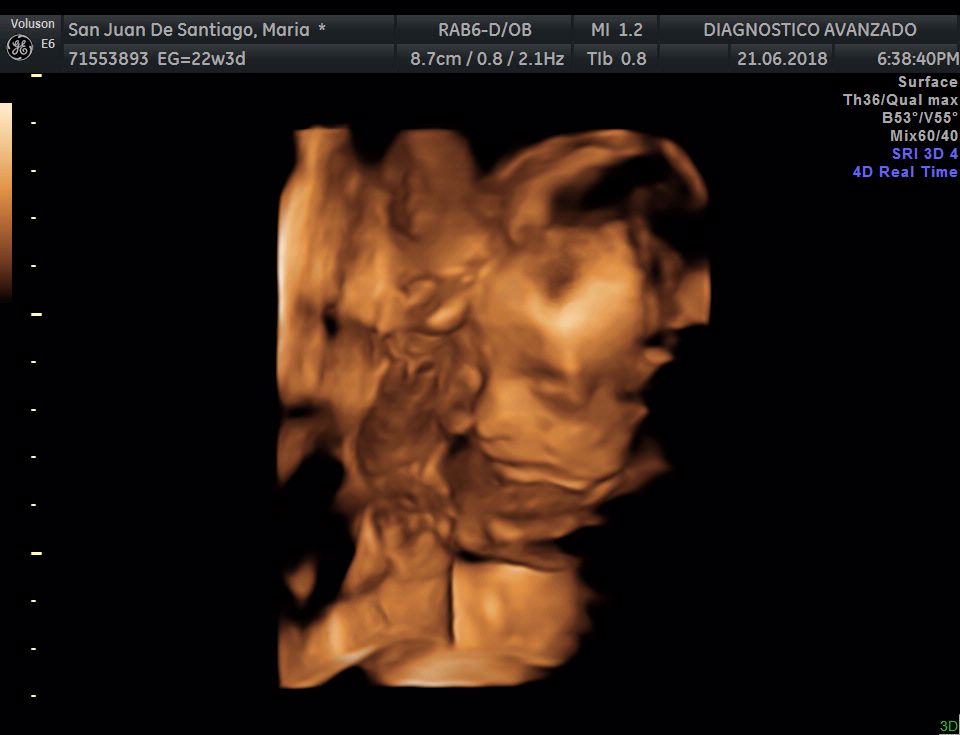

¡Hola a todos! Hoy hemos ido a hacer la tradicional ecografía 3D de la niña, os dejamos todo el material (aunque es un poco demasiado).